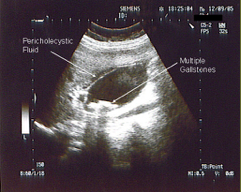

What diagnostic test is this?

US

In an US, what are the dark areas and what are the white areas?

Echogenic (solid / white) masses with “shadowing” behind (mobile)

What finding is this describing on an US?

Gallstones

US Of what structure?

Gallbladder